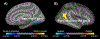

Results: One-year aerobic exercise increased peak VO2 by ∼10% (p < 0.001) while it did not change with stretching (p = 0.241). Cognitive composite scores increased in both the aerobic and stretching groups (p < 0.001 for time effect), although no group difference was observed. Total brain volume (p < 0.001) and mean cortical thickness (p = 0.001) decreased in both groups over time, while the reduction in hippocampal volume was smaller in the stretching group compared with the aerobic group (p = 0.040 for interaction). Across all participants, improvement in peak VO2 was positively correlated with increases in cognitive composite score (r = 0.282, p = 0.042) and regional cortical thickness at the inferior parietal lobe (p = 0.016).

Conclusions: One-year aerobic exercise and stretching interventions improved cognitive performance but did not prevent age-related brain volume loss in sedentary healthy older adults. Cardiorespiratory fitness gain was positively correlated with cognitive performance and regional cortical thickness.